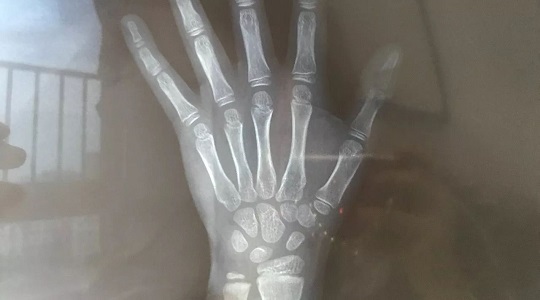

從下圖右邊的橫向柱狀圖可以看出,我兒子的“年齡身高”最加分,也就是9歲男孩139這個身高在全國孩子中處于70%以上水準(zhǔn)。骨齡拍出的片子顯示正常,因此得分54%,屬于中等。最最減分的是他的“遺傳身高”,因為媽媽腿長不爭氣,所以在這項上他只得分30%。